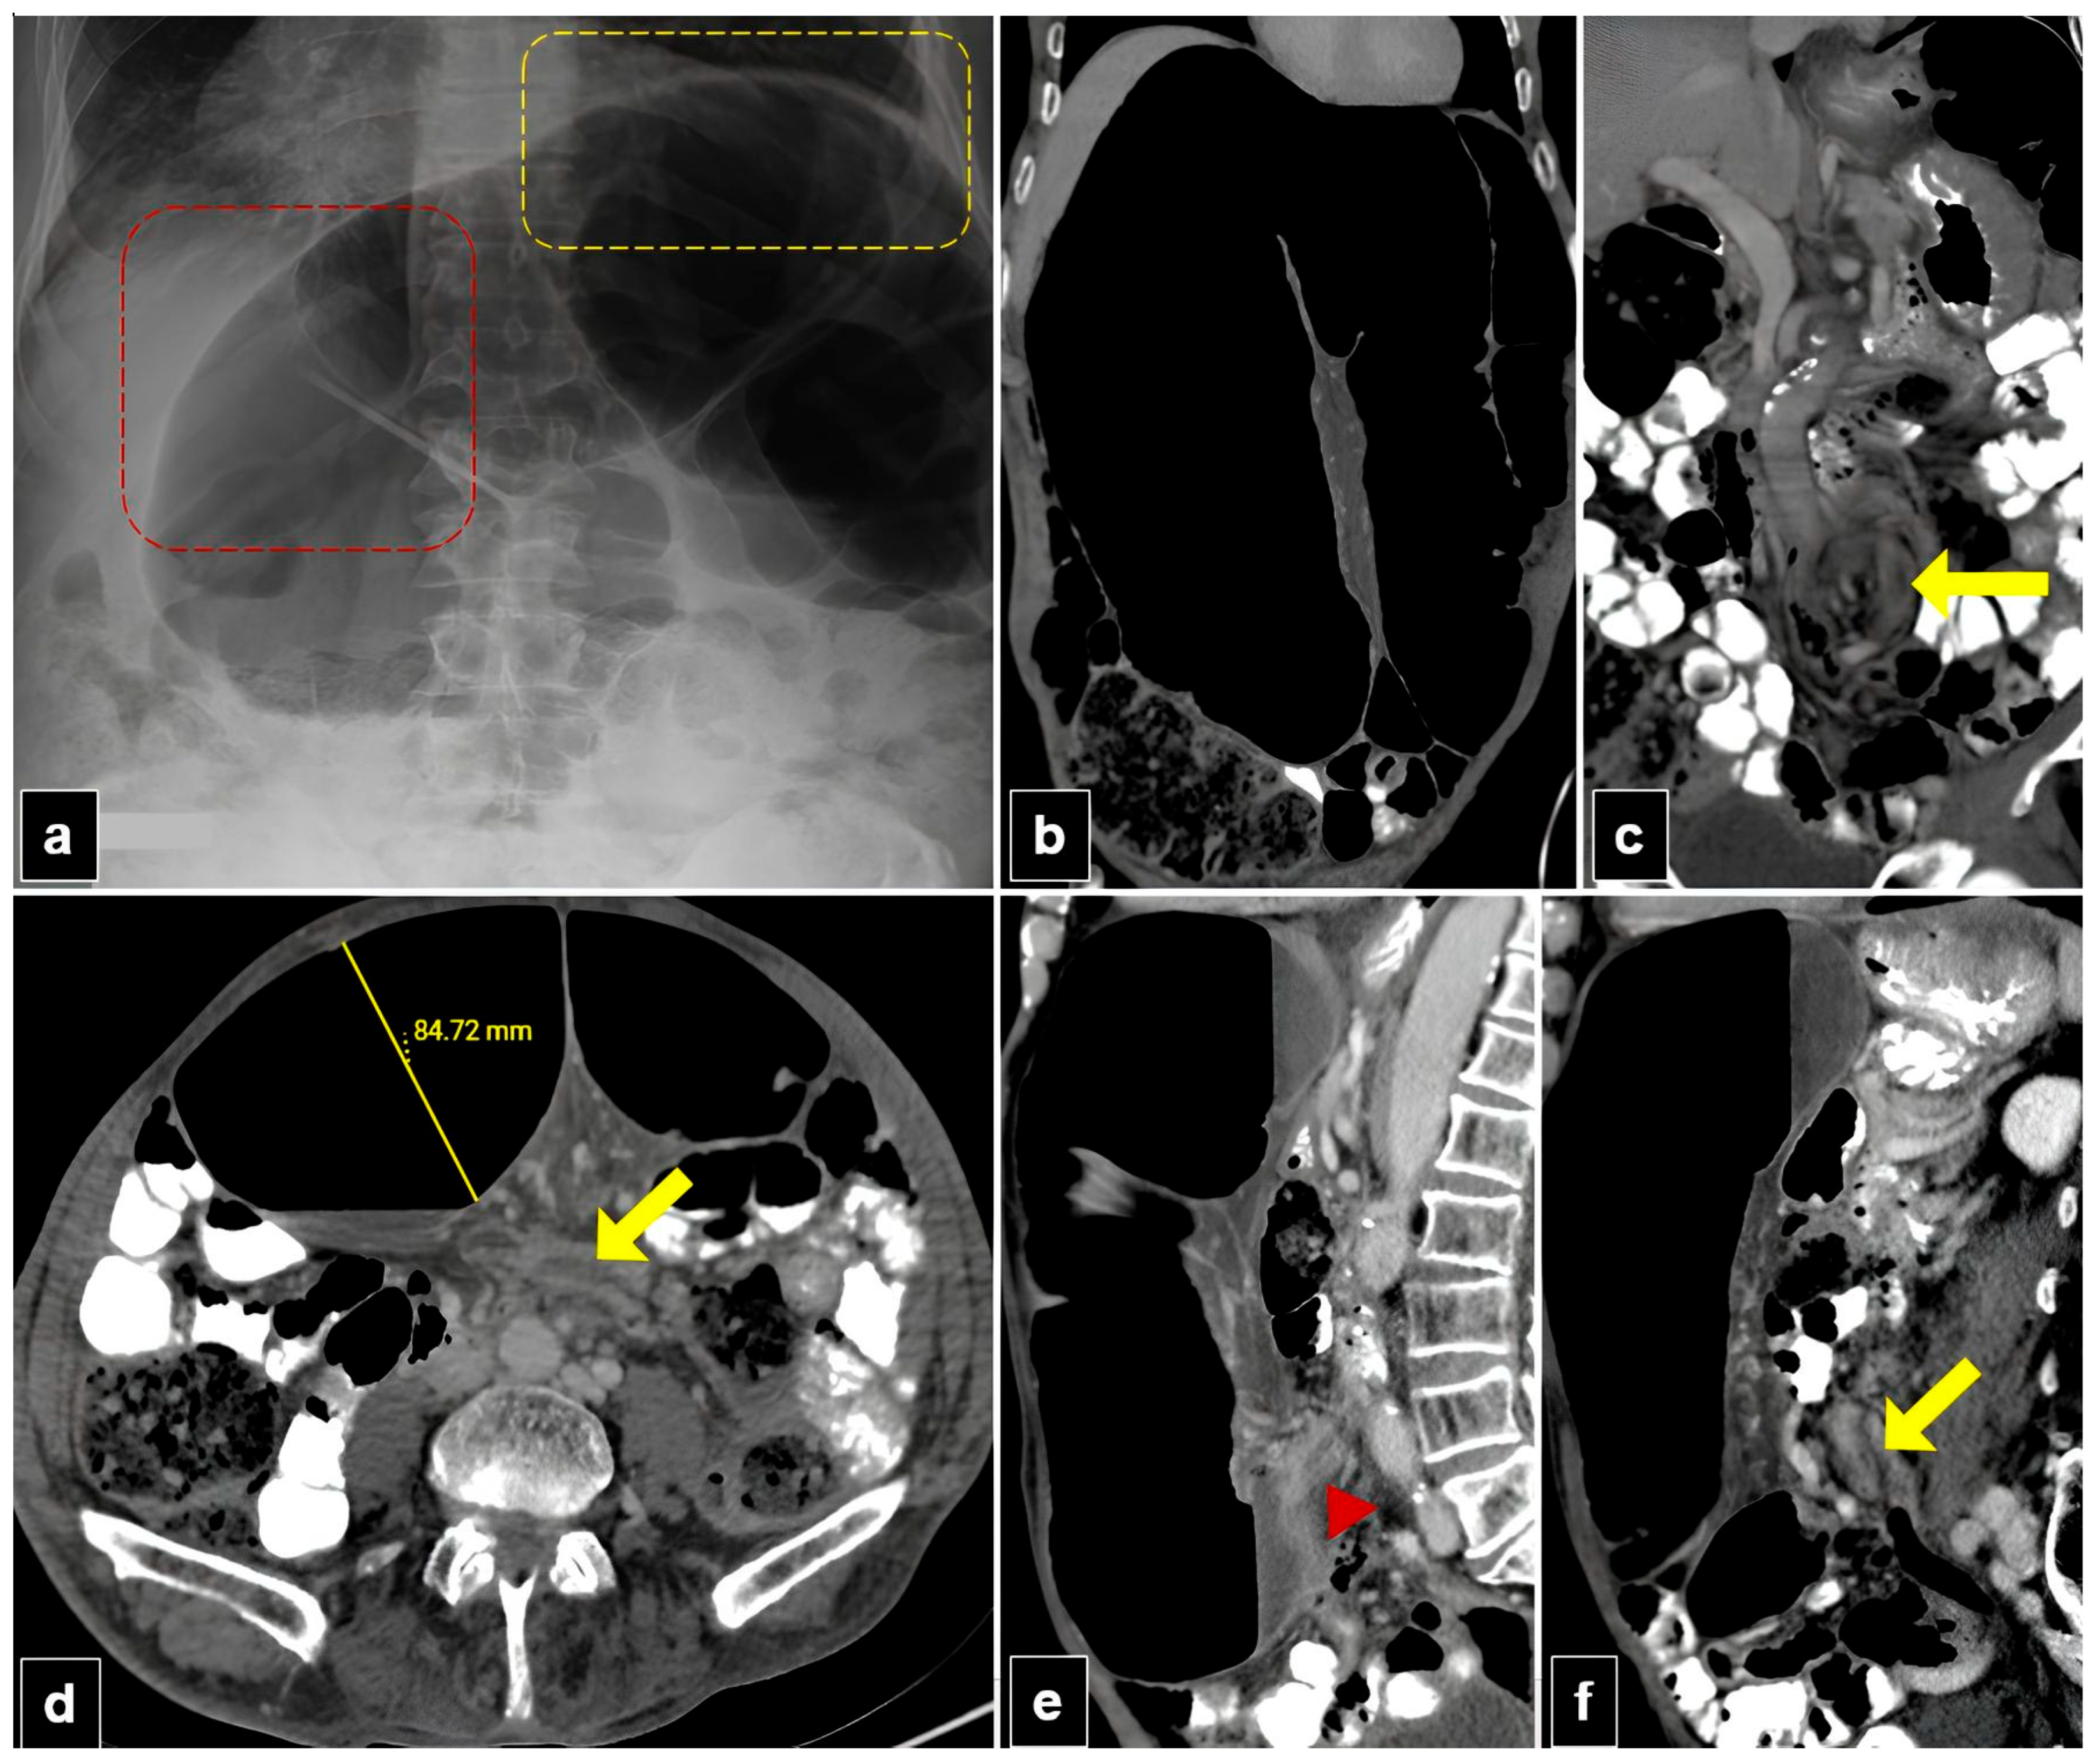

Figure 4. A 77-year-old male patient with organo-axial sigmoid volvulus presented with abdominal pain and distension for two days. (a) The plain abdomen radiograph reveals significant distension of the sigmoid loop, characterized by an inverted “U” shape, liver overlap sign (red dashed quadrilateral), and the sigmoid apex located beneath the left hemidiaphragm sign (yellow dashed quadrilateral). (b,c) Abdominal computed tomography (CT) images in the coronal plane show the inverted U-appearance of the distended sigmoid loop, and only one transition zone is present. Note the split wall sign caused by mesenteric fat tissue at the level of the transitional zone (yellow arrow). (d) The axial plan abdominal CT image shows the degree of distension in the sigmoid colon and the split wall sign located in the transition zone (yellow arrow). (e,f) The sagittal plane CT images of the abdomen show a single transition zone (red arrowhead) and a split wall sign (yellow arrow).